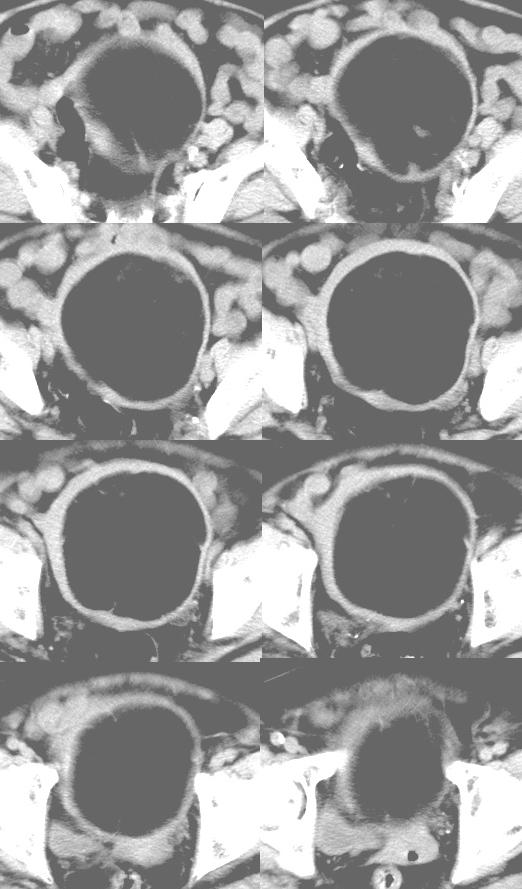

患者,女,74岁,无不适,b超示盆腔包块。

子宫前上方巨大脂性肿物,肿物边缘为较厚软组织密度影,其内缘欠光整,脂性密度中央见结节状软组织密度影“漂浮”,肿物与子宫前壁关系密切,考虑1脂肪瘤2皮样囊肿3肌瘤脂样变

请加大窗宽观察,内是脂肪吗?

ct值-90hu